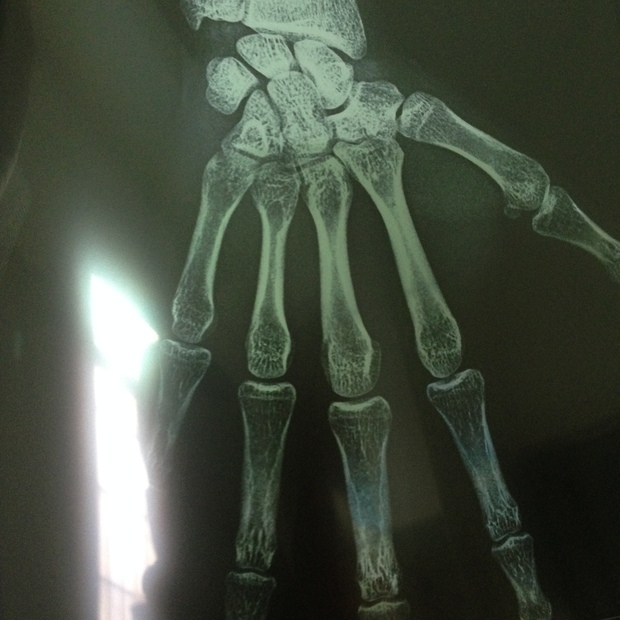

请问从这张图片上看我的骨骼线闭合没?骨龄是

480x640 - 40KB - JPEG

男 20岁 大家帮忙看一下我的骨骼线闭合没有?

620x620 - 116KB - JPEG